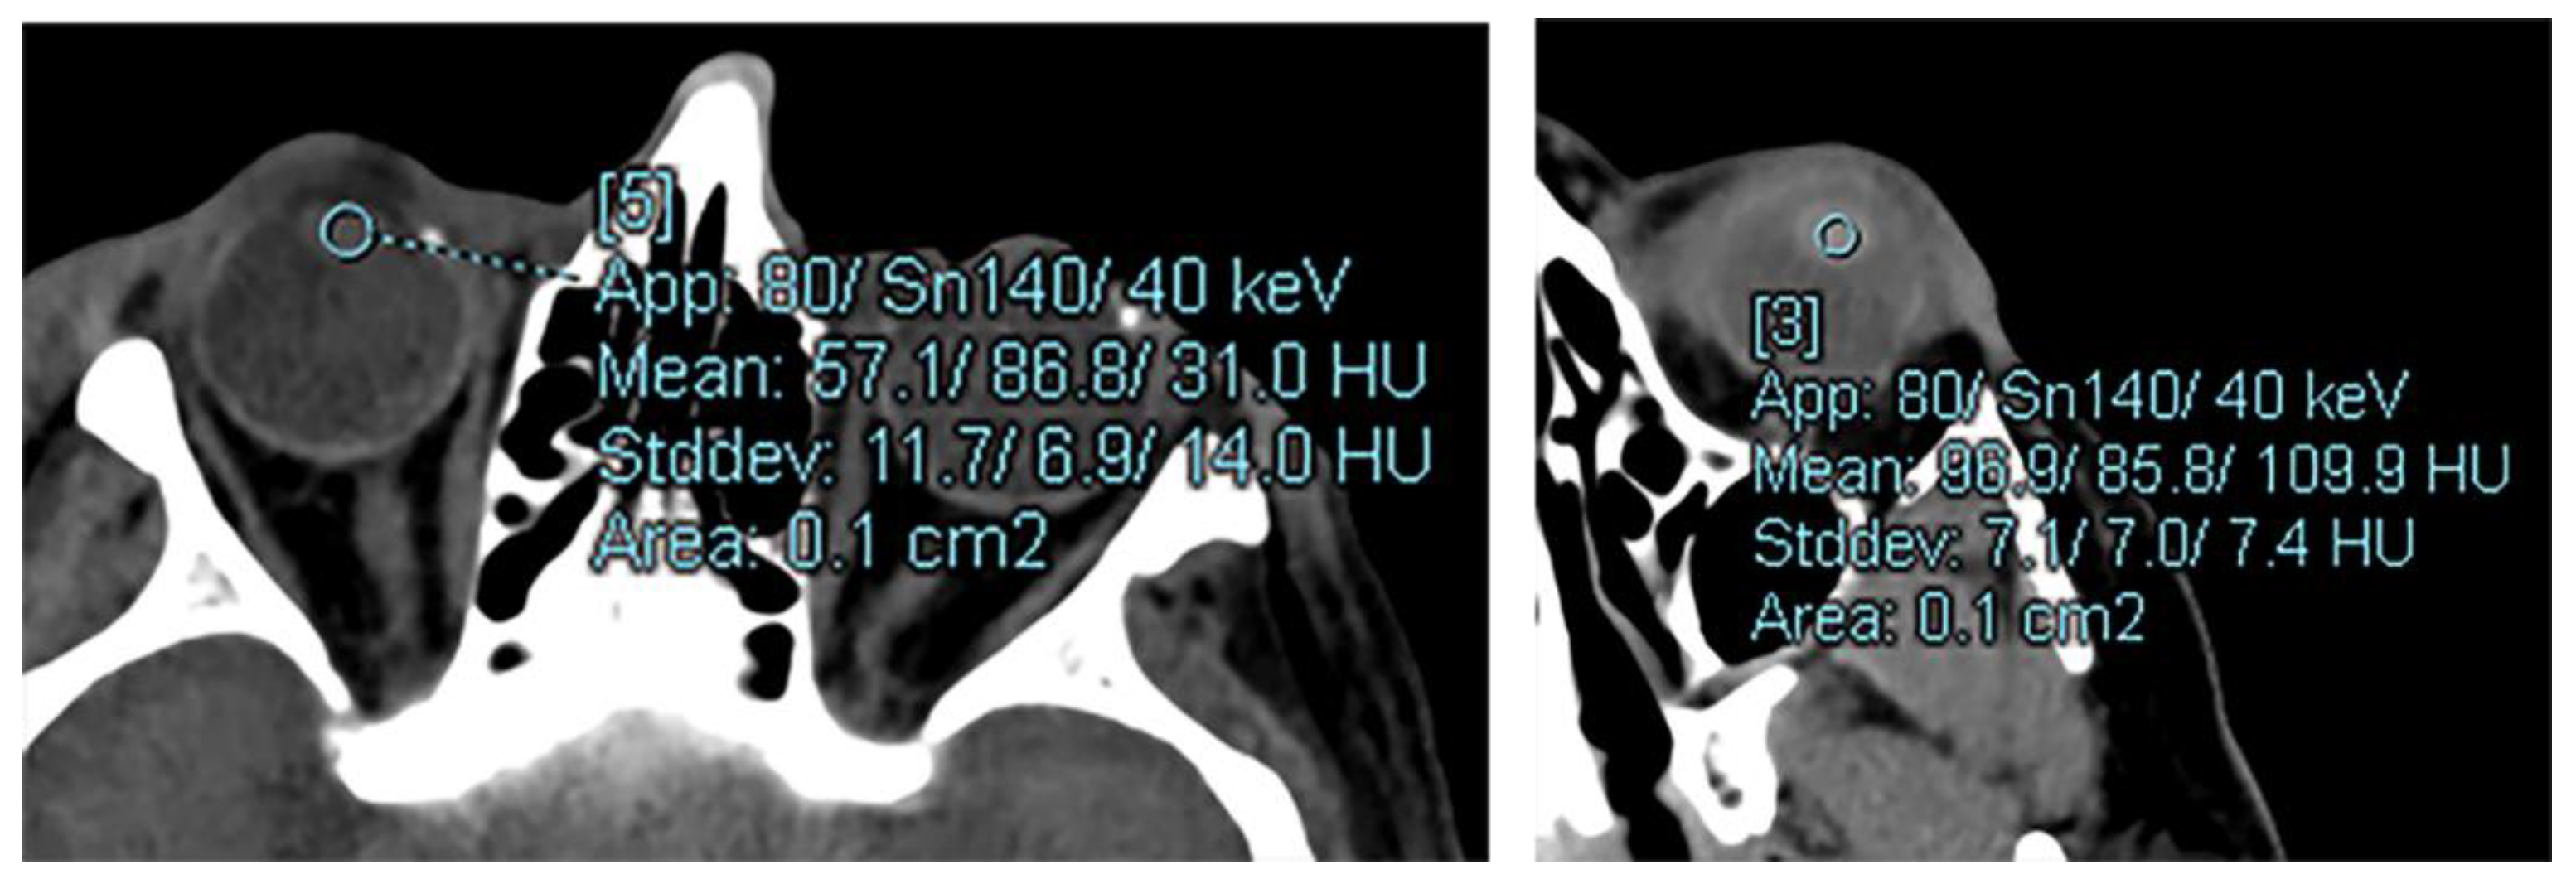

2.2. Image Acquisition

2.3. Image Analysis